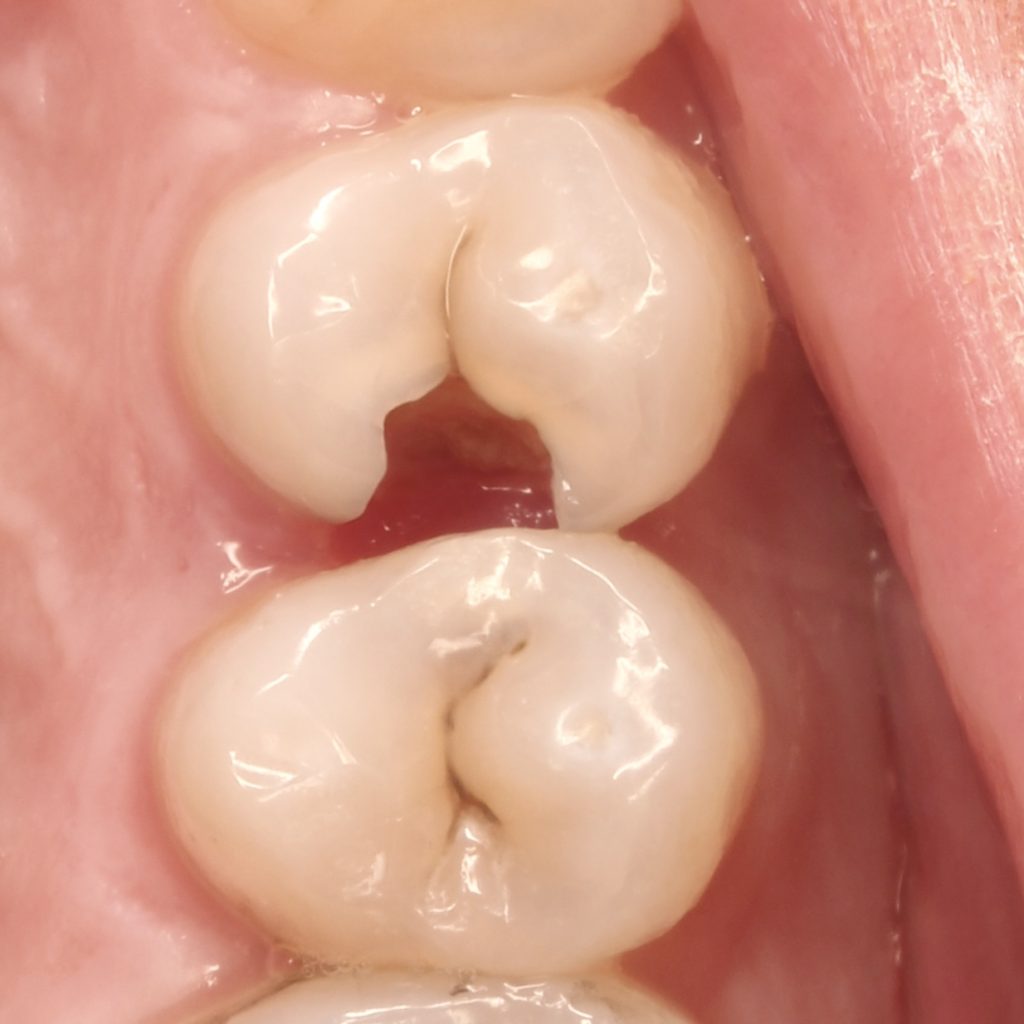

A 22 years old patient came to the clinic suffering from severe spontaneous pain. The diagnosis was acute irreversible pulpitis. The use of CDD is crucial here to ensure the CRE. After finishing endodontic treatment we used polyethylene fibers to enhance the bond strength and the strength of the tooth. Then the use of glass fibers (ever X composite) as a dentin replacement material before the final layer. After finishing. Polishing protocol with eve twist was done to gain the final polish